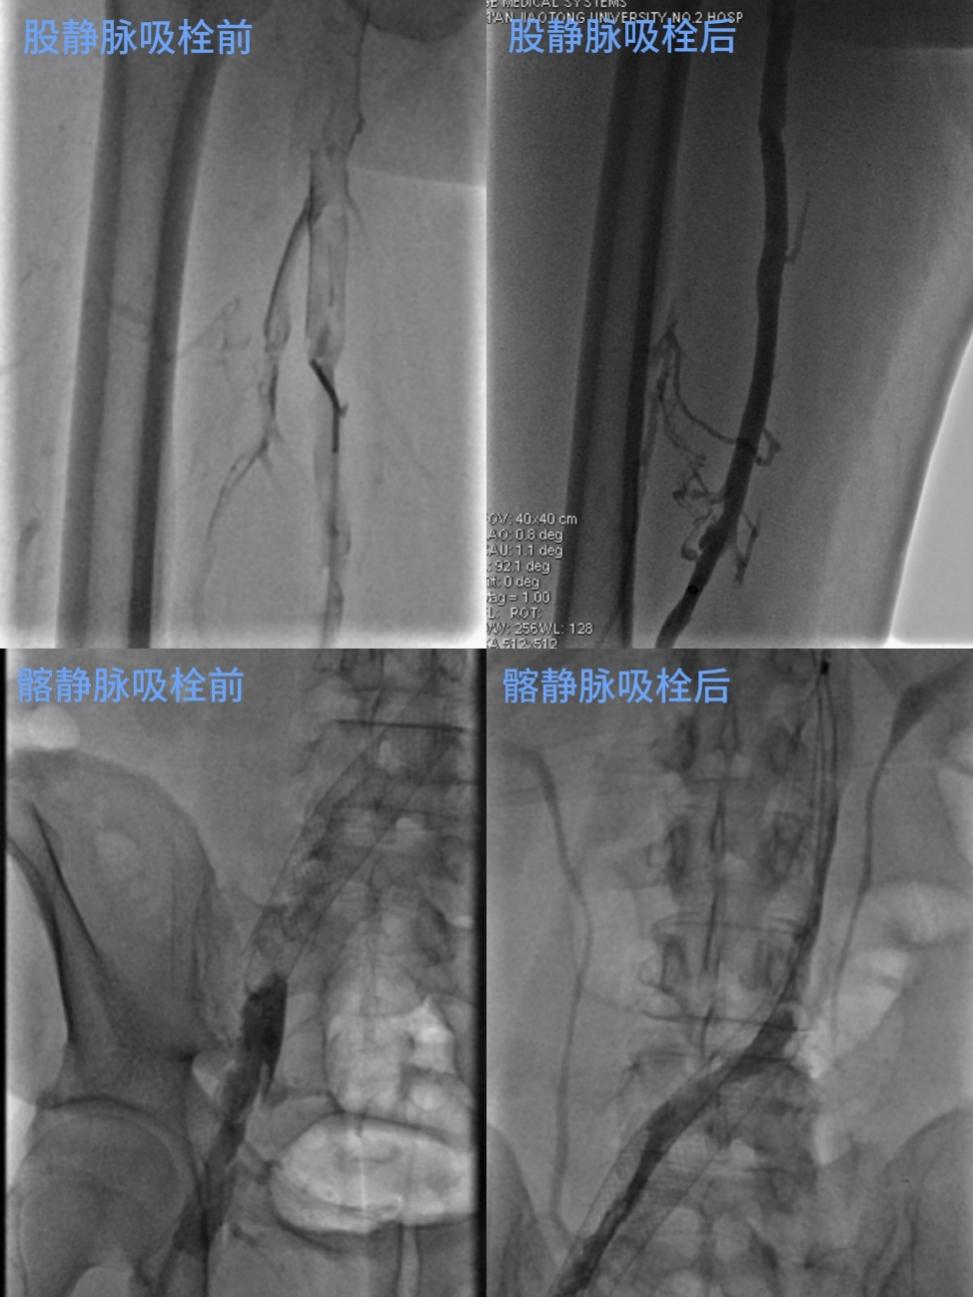

图为患者术前术后造影对比

鉴于患者已出现严重的运动障碍,且存在再次发生肺栓塞的高风险,血管外科主任马建仓主任医师和李宗禹主治医师深夜迅速带领团队,开通绿色救治通道。医护人员快速集结,紧急手术,实施了“下腔静脉滤器置入术、下肢深静脉机械血栓清除术、置管溶栓术及球囊扩张术”,一体化的诊治流程为患者减轻了经济负担,达到了彻底高效的治疗效果。手术过程高效流畅,成功恢复了血管的通畅性,有效防止了潜在的生命危险。